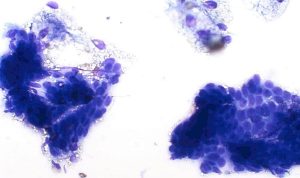

Sebaceous adenomas (and more commonly, nodular areas of sebaceous hyperplasia) and sebaceous epitheliomas yield cohesive groups of epithelial cells with abundant foamy, lipid-rich cytoplasm and small, uniform nuclei. The presence of mature sebocytes with minimal pleomorphism supports a benign process; however, increased numbers of smaller basal cells raise suspicion for epithelioma (Figure 13).

Figure 13 – Cytological features of a sebaceous epithelioma. The smear shows clusters and sheets of basaloid epithelial cells with some having abundant finely vacuolated, foamy cytoplasm consistent with sebaceous differentiation. Nuclei are round to oval with smooth chromatin and small nucleoli. Modified Wright’s stain, ×40 objective.